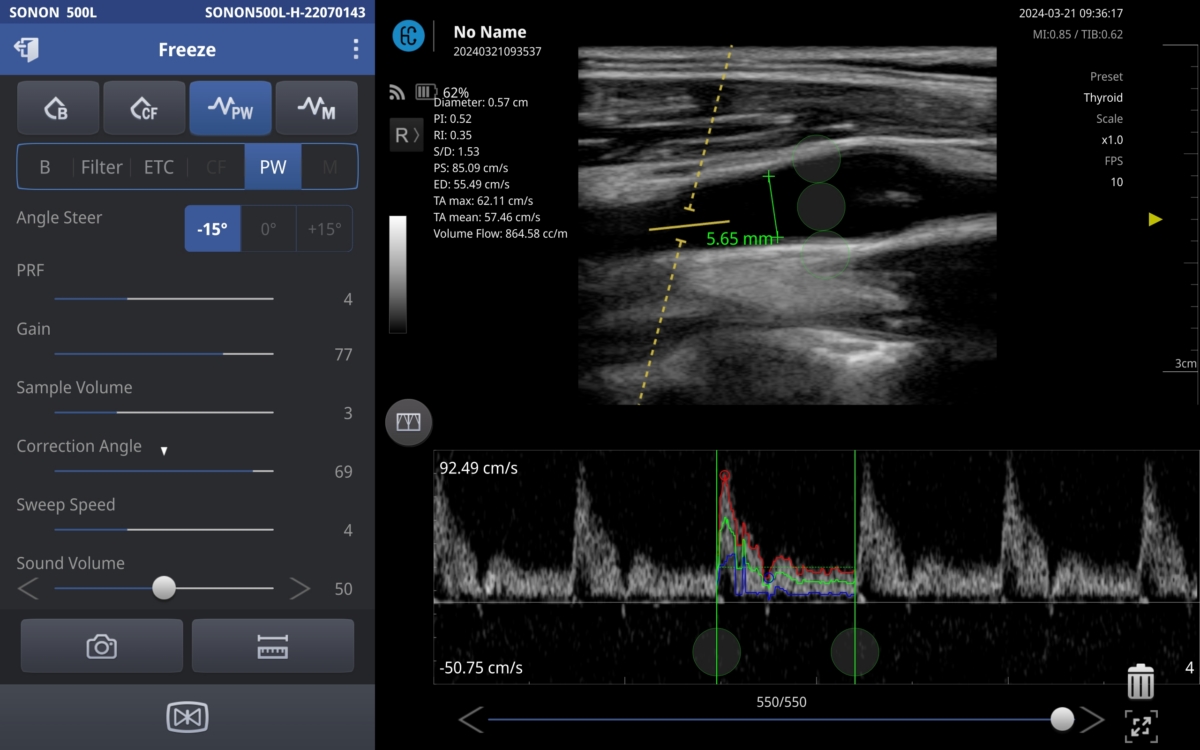

휴대용 초음파는 상대적으로 가격이 저렴하고 휴대가 간편한 장점이 있지만 투석 환자의 팔, 다리 등의 정밀한 혈관을 보기 위해선 높은 화질과 혈관의 상태를 파악할 수 있는 혈류량 측정 등의 특수기능이 요구된다.

힐세리온의 소논 500L은 VSETM 기술을 통해 기존 모델 대비 3배 이상의 화질을 향상시켰고, 휴대용 초음파에 처음으로 혈류량 측정 기능을 탑재해서 투석 환자의 혈관을 정밀하게 측정이 가능하다.